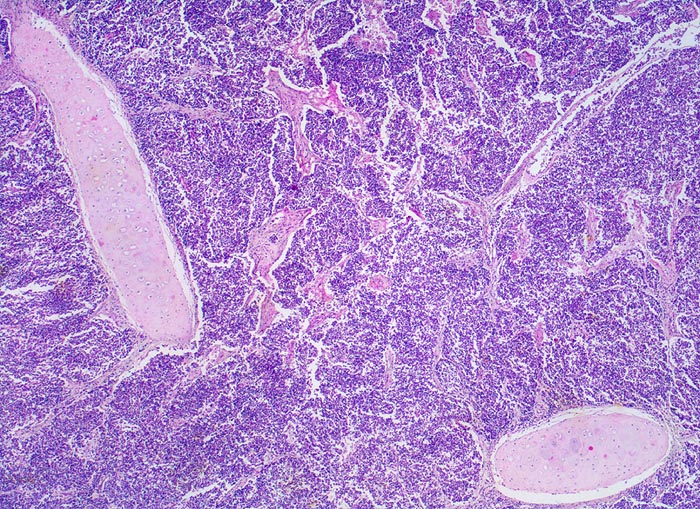

kleinzelliges Bronchuskarzinom

Das Karzinom bildet Stränge, die von schmalen Bindegewebssepten durchzogen werden. Das Tumorgewebe hat einen Segmentbronchus infiltriert und zerstört. Inseln von stehengebliebenem Bronchialknorpel werden vom Tumor umflossen. Aufgrund des hohen Kernanteils ist der Tumor blau gefärbt.

Inoperables metastasierendes Bronchuskarzinom. Nikotinabusus 70 Packyears.